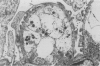

Rabbits given acute serum sickness (ASS) and treated with cyclosporin A (CyA) developed glomerular capillary thrombosis and cortical infarction, lesions not seen in unmodified ASS. Thirty-three NZW rabbits received a single intravenous injection of 250 mg/kg bovine serum albumen (BSA) with or without endotoxin (5 micrograms/kg) on day 0. Groups of rabbits were given intramuscular CyA as follows: 15 mg/kg from day -2 to +8, or 25 mg/kg/day from day -20 to +3 or day 0 to 5. Signs of this renal injury were haematuria, transient proteinuria, glycosuria and oliguria and they occurred during the rapid phase of antigen elimination when immune complexes were being formed. Seventeen of the 33 rabbits developed glomerular capillary thrombi and 11 of 17 also had glomerular and tubular infarction. Electron microscopic examination showed that these lesions were associated with severe endothelial injury and platelet-fibrin-leucocyte thrombi. These changes were more severe in the groups given 25 mg/kg. The lesions were not seen in untreated rabbits and ASS, nor in normal rabbits given equivalent doses of CyA alone. A strikingly similar renal lesion has been seen in patients receiving CyA following bone marrow transplantation, and also in the haemolytic uraemic syndrome. The model we describe may be valuable for the study of the mechanisms of endothelial injury and thrombosis in the kidney.